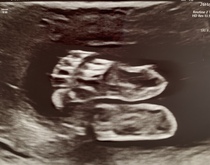

Here are a few photos of our little pickle - I'm obsessed with those little toes x

@danielasummer omg those feet I'm obsessed 👣👣👣